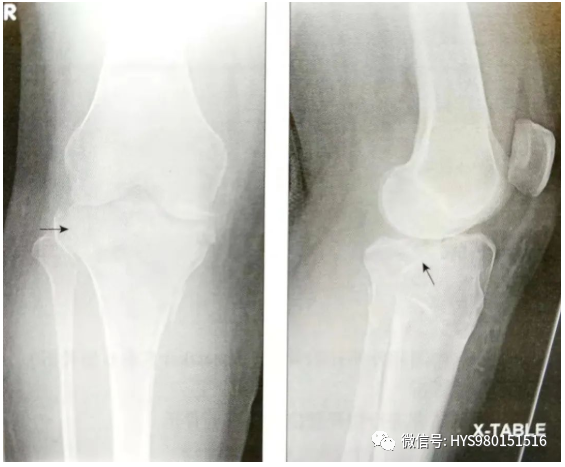

• 拍摄胫腓骨Ⅹ线平片;

• 评估膝关节半脱位的程度。

• 评估胫骨髁间嵴骨折,它在侧位片上显示最清楚;

• 观察胫骨平台的塌陷,正位片和侧位片。

什么是外固定架胫骨近端骨折:环形外固定架_https://www.jmylbn.com_新闻资讯_第5张

A:正位片;B:侧位片

• CT扫描能有效观察关节内骨折情况。标准的扫描应该包括轴位、冠状位和矢状位;

• CT可以提供完整的关节损伤信息,包括髁间嵴骨折,关节面塌陷的位置和程度,骨折块的大小,前交叉韧带撕脱骨折和后交叉韧带胫骨附着点撕脱骨折。